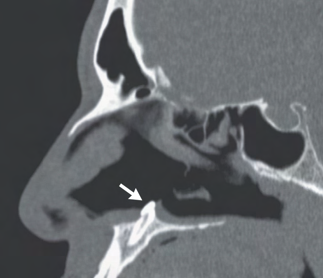

Recent studies indicate that Generative Pre-trained Transformer 4 with Vision (GPT-4V) outperforms human physicians in medical challenge tasks. However, these evaluations primarily focused on the accuracy of multi-choice questions alone. Our study extends the current scope by conducting a comprehensive analysis of GPT-4V's rationales of image comprehension, recall of medical knowledge, and step-by-step multimodal reasoning when solving New England Journal of Medicine (NEJM) Image Challenges - an imaging quiz designed to test the knowledge and diagnostic capabilities of medical professionals. Evaluation results confirmed that GPT-4V outperforms human physicians regarding multi-choice accuracy (88.0% vs. 77.0%, p=0.034). GPT-4V also performs well in cases where physicians incorrectly answer, with over 80% accuracy. However, we discovered that GPT-4V frequently presents flawed rationales in cases where it makes the correct final choices (27.3%), most prominent in image comprehension (21.6%). Regardless of GPT-4V's high accuracy in multi-choice questions, our findings emphasize the necessity for further in-depth evaluations of its rationales before integrating such models into clinical workflows.